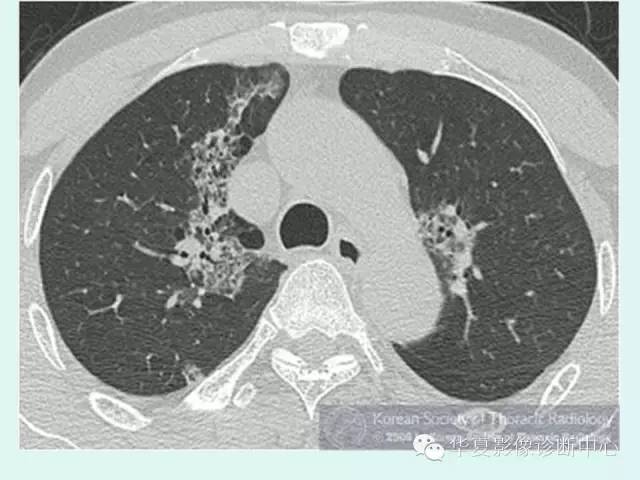

【病例】肺泡蛋白沉积症1例CT影像表现